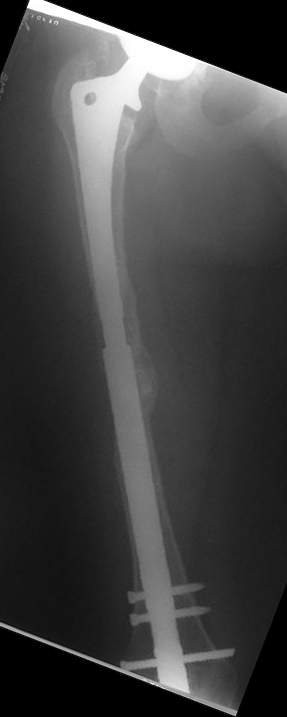

Female, rheumatoid, THA in 2003, car accident in 2006, failed plating. Nailing in Oct 2007. The nail is solid with hollow proximal part where the stem is docked. Last images are in 1 year after

nailing.